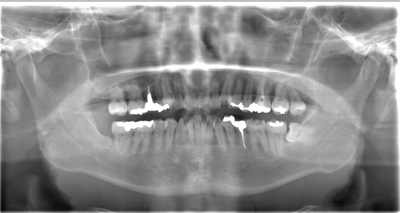

CASE 12

| 年齢・性別 | 29歳・女性 |

| 主訴 | 右下の親知らず抜きたい |

| 抜歯期間 | 30分 |

| 抜歯費用 | 約2,500円(保険内) 別途CT撮影で3,000円 (2022年8月現在) |

| 抜歯内容 | 右下親知らずの半埋伏抜歯 |

| 治療方針 |

右下の親知らずが斜めにはえていて、頭が半分出ている状態です。このままでは食べものが挟まりやすく、歯ブラシで汚れを落とすことが難しいです。 虫歯や歯周病になりやすくなってしまうため抜歯を行いました。 親知らずが下顎神経と近いため、CTを撮影して確認してから抜歯を行いました。 |

| 特記事項 |

下顎神経が親知らずと近い場合、親知らず抜歯を2回に分ける場合があります。 まず1回目に歯冠だけを抜きます。 手前の歯でストッパーになっている部分を落とすことで、歯根が移動して神経から離れます。 1年程経過をみて、2回目の抜歯を行います。 |